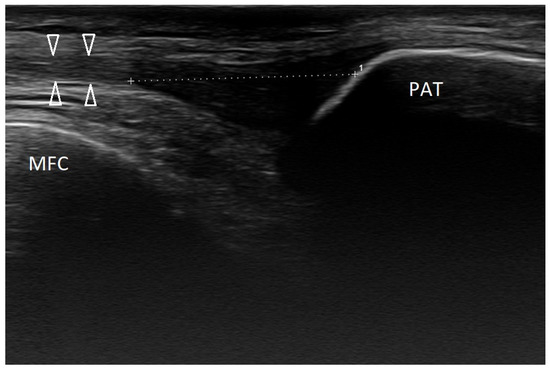

Basic Differences and Most Common Findings in Ultrasound Examinations of Musculoskeletal System in Children: A Narrative Literature Review

by Tomasz Poboży, Wojciech Konarski, Karolina Piotrowska-Lis, Julia Domańska, Kamil Poboży and Maciej Kielar

We present basic differences in the musculoskeletal ultrasound examinations between adults and children. Examiners who deal with adults on a daily basis have shared concerns about examining children. Such concerns may arise from the different approach to child ultrasounds, but they also come [...] Read more.

We present basic differences in the musculoskeletal ultrasound examinations between adults and children. Examiners who deal with adults on a daily basis have shared concerns about examining children. Such concerns may arise from the different approach to child ultrasounds, but they also come from differences in anatomical characteristics according to developmental age. We discuss the presence of growth plates, as well as non-mineralized parts of the bones. We also refer to the pathologies most often found in ultrasounds in early developmental stages. In the PubMed database, the set of keywords: “msk ultrasound in children”, “pediatric msk sonoanatomy”, “coxitis fugax”, “pediatric Baker’s cyst”, “Baker’s cyst ultrasonography”, “bone septic necrosis in ultrasonography”, “ultrasonography in juvenile idiopathic arthritis”, and “ultrasonography in juvenile spondyloarthropathies”, was used to identify a total of 1657 results, from which 54 was selected to be included in the article. We discuss the problem of osteochondritis dissecans, Osgood-Schlatter disease, examples of ligament injuries (especially in relation to the knee and ankle joints), exfoliation of growth cartilages, osteochondroma, exudates and inflammations affecting joints, and Baker’s cysts. In this way, we have collected useful information about the most common diseases of the musculoskeletal system in children. Full article

Show Figures

Figure 1